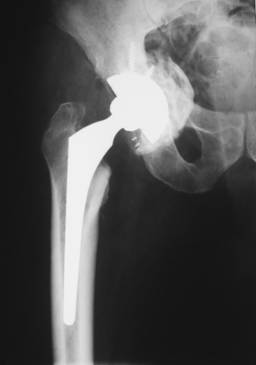

Artroplastiile s-au realizat in doua interventii operatorii la distanta de 6 luni, initial pe partea dreapta (fig. 2), unde s-a instalat initial decompensarea algica si apoi pe partea stanga (fig. 3), unde a fost necesara crearea unui nou fund al acetabulului cu ajutorul unui inel de ranforsare insurubat tip Brch-Schneider. Intre inel si acetabul s-a introdus o grefa osoasa cortico-spongioasa recoltata din creasta iliaca. Pe ambele parti, componenta femurala a fost de tip necimentat.

Fig. 2. Rezultatele imediate postoperatorii.